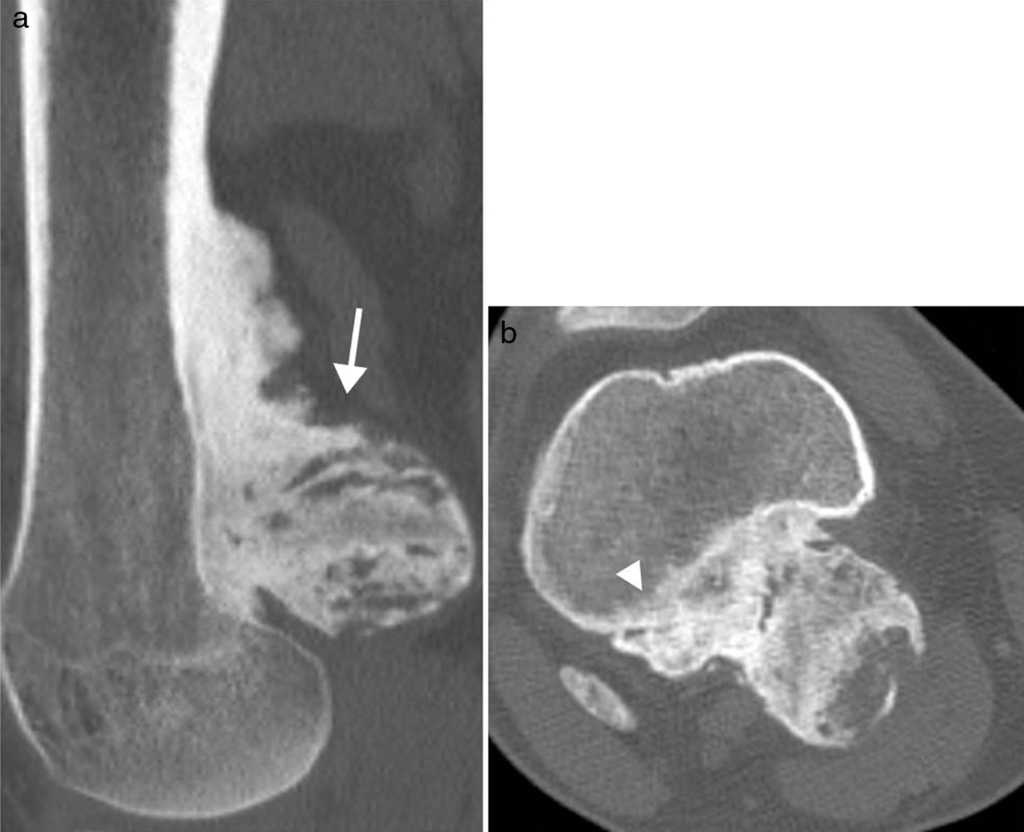

El segundo caso fue otro varón de 23 años con una tumoración dolorosa en el hueco poplíteo, que había crecido en el último mes. El paciente no tenía antecedente traumático ni fiebre o síndrome constitucional. A la palpación la tumoración era firme y no móvil. La radiografía simple mostró una lesión de localización metafisodiafisaria, dependiente de la cortical femoral y de dudosa continuidad con la medular, con morfología irregular y matriz osteoide (fig. 3). En la TC se confirmaron los hallazgos (fig. 4a) y, además, se detectó un área de posible afectación de la medular periférica (fig. 4b). Se completó el estudio con RM y gammagrafía ósea (no mostradas) y, ante la sospecha de malignidad, se realizó una biopsia con resultado de POPB.

En imágenes la POPB se identifica como una masa osificada, bien delimitada y de localización yuxtacortical, con una base amplia de implantación afectando al periostio8. El hueso subyacente presenta apariencia normal, sin afectación medular, esclerosis reactiva o periostitis2. Existe algún caso descrito en el que la POPB muestra continuidad con la medular ósea, por lo que la ausencia de este hallazgo típico no descarta la enfermedad2.

La POPB no requiere realización de biopsia en casos típicos, ya que la imagen y las características clínicas son suficientes para establecer el diagnóstico. Se recomienda un seguimiento de 6 meses9. En casos atípicos, es obligatoria la biopsia y el estudio anatomopatológico para establecer el diagnóstico y descartar el osteosarcoma parostal, ya que las manifestaciones raras, como la continuidad con la medular ósea o la afectación de la cortical, deben ser diferenciadas de la patología maligna.